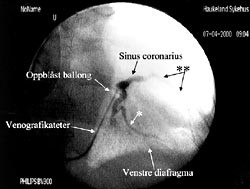

Etter punksjon av v. subclavia og innsetting av veneintroduser, innføres en lang ledesonde til høyre atrium under røntgengjennomlysning, oftest i flere plan. Over ledesonden innføres et spesiallaget introdusersystem med en 40 – 45 cm lang introduserhylse over en 54 cm lang dilatator til sinus coronarius. Etter at introduseren er plassert i stabil posisjon i sinus coronarius, innføres et 80 cm langt venografikateter med en lateksballong ved tuppen på kateteret til sinus coronarius. Denne ballongen kan blåses opp til en diameter på 10 mm og okkludere sinus coronarius helt eller delvis mens man injiserer kontrast og tar røntgenbilde av koronarvenene. Koronarveneanatomien har vist seg å variere fra pasient til pasient. Venogrammet gir et bilde av hvilke vener som er tilgjengelige for plassering av pacemakerledningen (fig 1). Man tilstreber å få spissen av pacemakerledningen plassert distalt i en lateral koronarvene. Til tross for spesielle vinklinger av ledningen er det ofte meget vanskelig å få plassert spissen på ledningen i ønsket posisjon. Kriteriene på en god posisjon av ledningen er at terskelen for stimulering av venstre ventrikkel ved 0,5 ms pulsvarighet er maksimum 3,0 V og at R-bølgen> 4,0 mV. Det må ikke forekomme stimulering av n. frenicus med diafragmastimulering ved høyeste spenning 7,5 V. Elektrogrammet avledes fra ledningen i koronarvenen og elektrogrammets konfigurasjon avgjør om ledningen er korrekt plassert over venstre ventrikkel.

For å innføre pacemakerledning til koronarvener kreves erfaring i hjertekateterisering. Man må ha mulighet for venografi av koronarvenene (fig 1). Ofte kan ikke de laterale koronarvener påvises ved venografi (15). Prosedyren som krever gjennomlysning i flere plan, tar fra en time til 4 – 5 timer. For våre fem pasienter var gjennomsnittlig prosedyretid 187 ± 40 minutter. Dersom man ikke får ledningen langt nok perifert i koronarvenen, kan den forskyve seg sentralt, noe som vil kunne føre til stimuleringssvikt (pasient 5) og eventuelt også til stimulering av n. frenicus med diafragmarykninger som konsekvens.